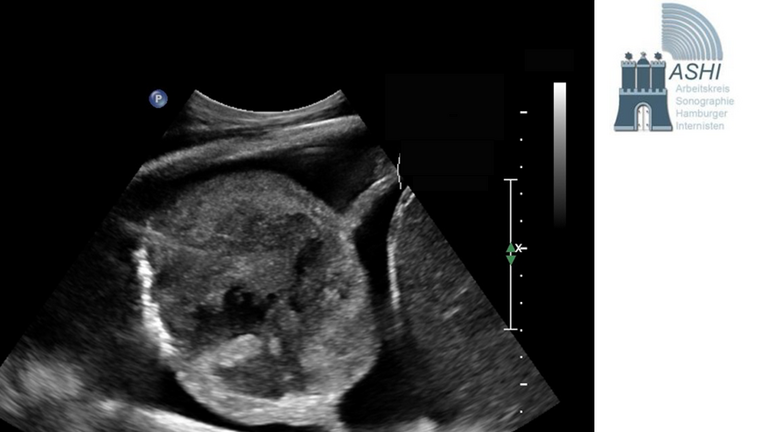

30 Jahre Kontrastmittelultraschall des Abdomens - wo stehen wir heute